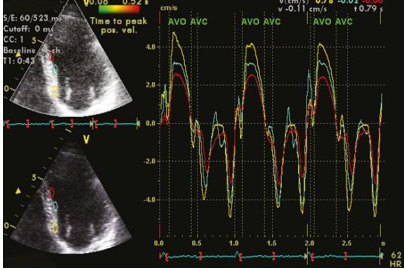

Tissue Doppler Imaging (TDI) and Strain and Strain Rate Imaging (SRI)

The Doppler technique is employed in measuring myocardial velocities due to the contrasting signal characteristics between blood and myocardium. There are notable differences in signal amplitudes and Doppler frequencies between these two components. While the speed of myocardial motion is considerably lower compared to blood flow, the amplitude of myocardial signals is significantly higher. These distinctions enable the implementation of filters that selectively isolate myocardial velocities while rejecting echo signals originating from the blood pool. The recording of velocities can be achieved using either color Doppler or pulsed wave Doppler techniques.

The introduction of myocardial velocity imaging dates back to the early 1990s, [51], [52] and since then, it has become a well-established method for quantifying both left ventricular (LV) systolic and diastolic function. Real-time imaging of myocardial motion allows for the visualization of color-coded velocities overlaid on a 2D grayscale image. The frame rate for 2D color Doppler typically ranges between 80 and 200 frames per second, depending on the sector width, and is usually set higher than that of simultaneous grayscale images. The analysis of myocardial velocities can be performed offline, as shown in [Figure 5].

Clinical application of tissue Doppler velocity imaging extends to various areas. It can be utilized for diagnosing myocardial ischemia, assessing patients with diastolic dysfunction, and aiding in the selection of suitable candidates for cardiac resynchronization therapy through the evaluation of ventricular dyssynchrony, as depicted in [Figure 6]. Tissue Doppler velocity imaging plays a crucial role in these clinical scenarios, providing valuable information for diagnosis, evaluation, and treatment decisions.